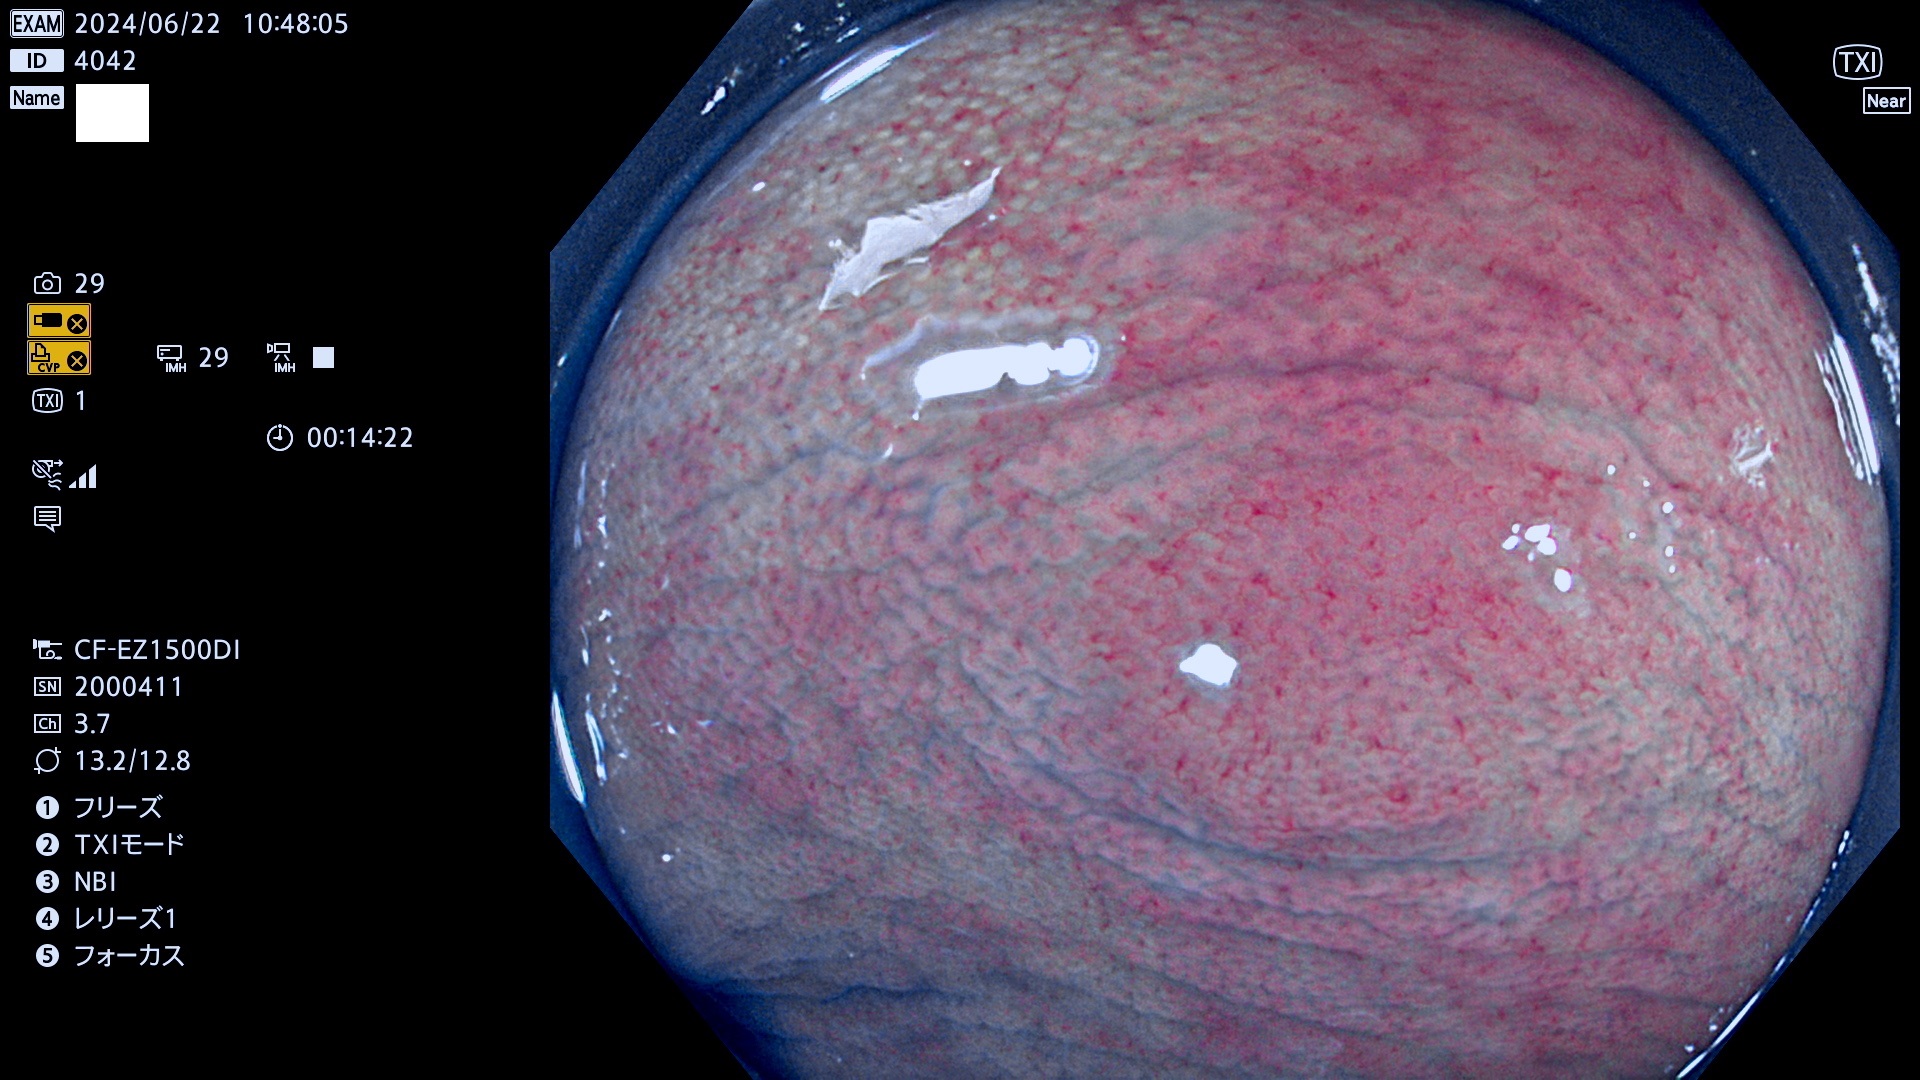

完全に平坦な物をUb、陥凹している物をUcと呼びます。最も発見が難しく危険な病変です。

毎週の検査(木・金・土・日)に発見されたUb、Uc型・腺腫を、その週の日曜の夜にUPし1週間、提示します。

抽出の対象期間 2024年6月20日〜6月24の5日間(40件の検査)6件 (6/40=15%)